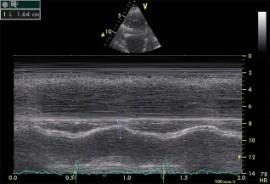

Echokardiografie: LEVÁ KOMORA bez dilatace a hypertrofie, s normální systolickou funkcí a regionální kinetikou kromě D shape, EF LK 55-60%. Diastolická funkce: porucha relaxace LK. PRAVÁ KOMORA FAC PK 18%, TAPSE 13 mm, Vt 9 cm/s, dilatace a hypertrofie PK, těžká prekapilární PH, odhadovaný PASP 90 mmHg, MPAP 55 mmHg, malý perikardiální výpotek

Echokardiografie: LEVÁ KOMORA bez dilatace a hypertrofie, s normální systolickou funkcí a regionální kinetikou kromě D shape, EF LK 55-60%. Diastolická funkce: porucha relaxace LK. PRAVÁ KOMORA FAC PK 19%, TAPSE 17 mm, Vt 9 cm/s, dilatace a hypertrofie PK, těžká prekapilární PH, odhadovaný PASP 130

mmHg, perikardiální výpotek